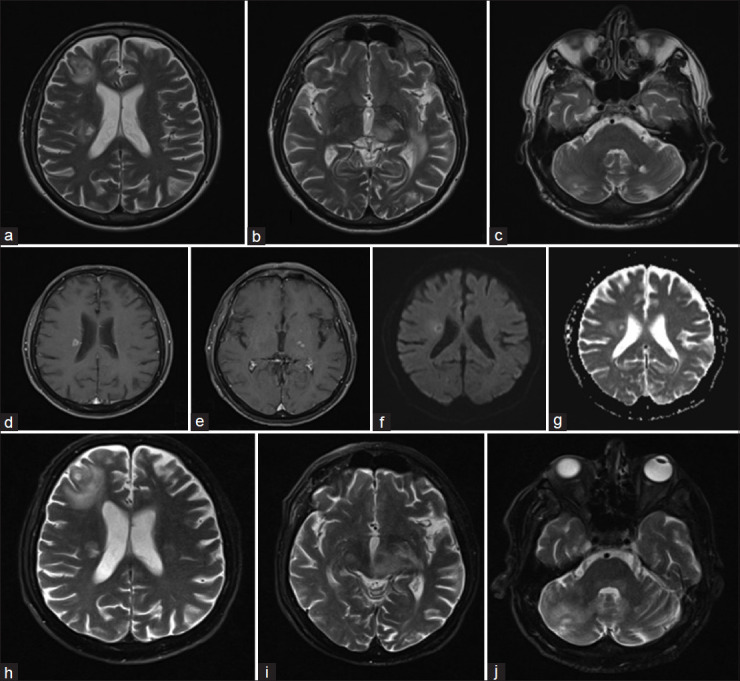

炎性脱髓鞘假瘤(IDP)在临床表现和影像学特征方面与颅内肿瘤相似。具有马尔堡样特征的IDP是一种严重形式的炎症性脱髓鞘性脑脊髓炎,其特点是起病剧烈,病程积极,无缓解,存在肿瘤样中枢神经系统脱髓鞘病变。脑磁共振成像IDP的主要特征包括开放或不完整的环形增强,低T2边缘,外周扩散受限,没有或轻微的肿块效应,以及病灶周围水肿。在脑磁共振波谱(MRS)中,观察到谷氨酸、胆碱和乳酸盐峰升高;然而,脑MRS的发现可能是非特异性和非鉴别的。病理结果显示明显的血管周围淋巴浸润,主要由白细胞共同抗原(LCA)+和PAX5+ B淋巴细胞组成(免疫组化染色),实质和血管周围巨噬细胞(CD68+), Luxol Fast Blue染色可见髓磷脂球,髓磷脂优先丢失,相对轴突保存,轴突球状体形成(肿胀),反应性星形细胞增生(GFAP+和ATRX-)。斑块周围的髓鞘比背景轴突薄。对以往病例报告的回顾显示,对具有马尔堡样特征的IDP进行及时积极的免疫抑制治疗可能会产生良好的反应。以高剂量皮质类固醇开始治疗周期,随后使用环磷酰胺、米托蒽酮、利妥昔单抗或阿仑单抗进行救援性免疫抑制治疗,显示出积极的结果。此外,使用b细胞消耗药物(如rituximab和ocrelizumab)进行维持性免疫抑制治疗,显示出控制疾病活动和改善长期预后的潜力。

Inflammatory demyelinating pseudotumor (IDP) mimics intracranial neoplasms in terms of both clinical presentation and imaging features. IDP with Marburg-like features represents a severe form of inflammatory demyelinating encephalomyelitis, marked by a dramatic onset, aggressive course, absence of remission, and the presence of tumor-like central nervous system demyelinating lesions. Key features of IDP in brain magnetic resonance imaging include open or incomplete ring enhancement, low T2 rim, peripheral diffusion restriction, absent or mild mass effect, and perilesional edema. In brain magnetic resonance spectroscopy (MRS), elevated glutamate, choline, and lactate peaks are observed; however, brain MRS findings can be nonspecific and nondifferentiating. Pathologic findings show prominent perivascular lymphoid infiltrates consisting predominantly of leukocyte common antigen (LCA)+ and PAX5+ B lymphocytes in immunohistochemistry staining, parenchymal and perivascular macrophages (CD68+), some with visible myelin globules on Luxol Fast Blue staining, preferential loss of myelin with relative axonal preservation and the formation of axonal spheroids (swellings), reactive astrocytosis (GFAP+ and ATRX-), and remyelination with thinner myelin sheaths than background axons at the periphery of the plaque. A review of previous case reports revealed that prompt aggressive immunosuppression therapy in the IDP with Marburg-like features may lead to a favorable response. Initiating treatment with a cycle of high-dose corticosteroids followed by rescue immunosuppressive therapy using cyclophosphamide, mitoxantrone, rituximab, or alemtuzumab demonstrated positive outcomes. In addition, maintenance immunosuppressive therapy with B-cell-depleting agents, such as rituximab and ocrelizumab, showed potential for controlling disease activity and improving long-term prognosis.